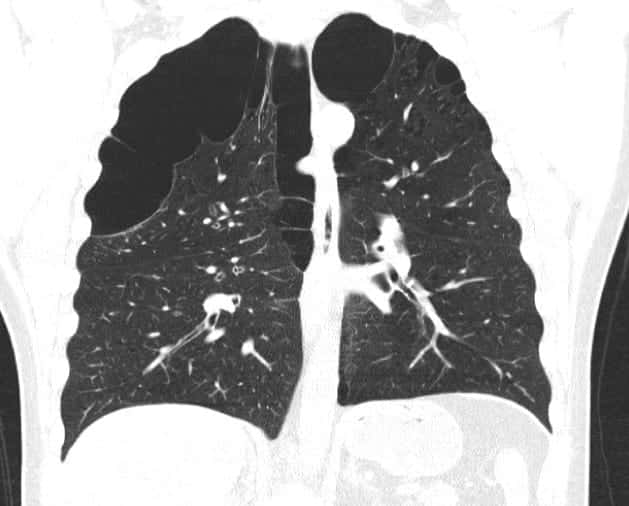

COPD Lungs Vs Normal Chest X Ray